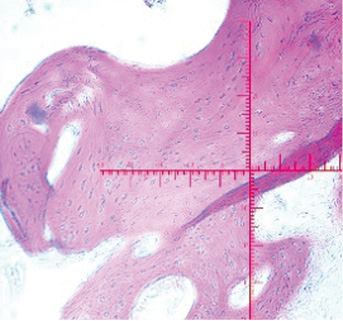

Микроскопический вид (ув. 40) |

2-я экспериментальная группа (левый сустав): определяется ограничение движений в суставе, «минус-ткань», составляющая 1/3 толщины кратера дефекта, с ровными гладкими краями, граница между новообразованной тканью и сохранённым хрящом прослеживается чётко. Микроскопически полость дефекта полностью заполнена новообразованной молодой хрящеподобной тканью. Хондробласты более интенсивно пролиферируют, они более дифференцированы, лакуны располагаются теснее. Надхрящница полностью сформирована. Наблюдается интенсивный рост хряща по аппозиционному типу.

3-я экспериментальная группа (левый сустав): определяются незначительные ограничения движений в суставе, а также «минус-ткань», составляющая 1/4 толщины сформированного дефекта, с ровными гладкими краями, граница между новообразованной тканью и сохранённым гиалиновым суставным хрящом прослеживается чётко. Микроскопически полость дефекта заполнена хрящеподобной тканью с наличием лакун и межклеточного вещества. Отмечается пролиферация хондробластов и их дифференцировка. Хрящеподобная ткань плотно сращена со стенками полости, фиброретикулярная ткань не обнаружена.

За 3 мес во всех группах произошли макро- и микроскопические изменения, отражённые в табл. 2.

Таблица 2. Макро- и микроскопическая оценка спустя 3 мес от начала эксперимента

Table 2. Macro- and microscopic evaluation after 3 month from the start of the experiment